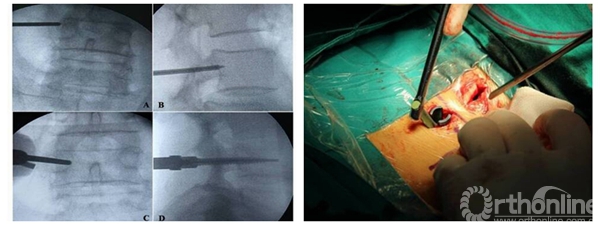

经皮椎弓根螺钉固定术、微切口椎管减压固定术、内窥镜脊柱手术、穿刺射频消融、术中放疗术、颈椎微创融合固定术等的应用和创新,标志着骨科研究所微创脊柱外科技术水平与国际同步,特别是经皮螺钉固定术水平达到国际先进水平,率先应用横突探触法及多点进钉法,使手术时间明显缩短,X线曝光率减少一半以上;在国际上最先对长臂螺钉经皮植入进行研究和改造并取得突破,该项技术应用规模省内领先。